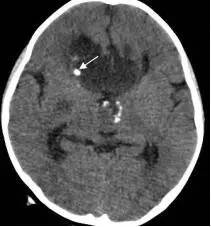

图2.术前MRI

白色箭头指示肿瘤下极达枕大孔区